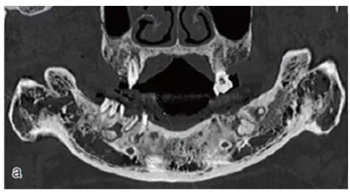

術(shù)前拍攝錐形束CT,進行三維重建和種植方案規(guī)劃。從CT圖像中可以看出頜骨內(nèi)有骨島和殘根,為避免種植體植入骨島區(qū),考慮在兩側(cè)頦孔區(qū)種植4~5顆種植體,采用套筒冠進行即刻修復(fù)。從重建的結(jié)果中可知前牙區(qū)牙槽嵴呈刀刃狀。種植方案為:對前牙區(qū)牙槽嵴進行截骨修整,并在兩頦孔之間的區(qū)域內(nèi)植入5顆種植體。

圖15 種植方案的規(guī)劃:a.患者的CT圖像的截面圖,圈紅處為骨島;b.患者摘掉活動義齒后的下頜;c.患者上下頜骨的CT三維重建;d.下頜骨截骨后模擬植入5顆種植體